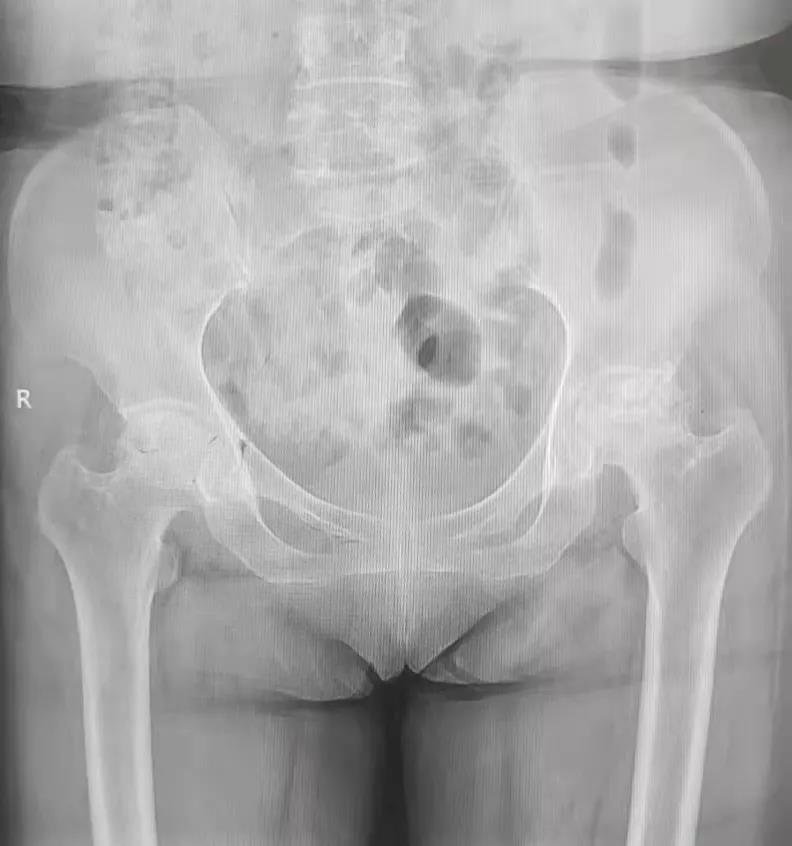

2021年11月16日,来自玉林容县的廖女士和封女士相约到我院髋关节一科住院治疗,她们既是同乡,也是相识多年的好友,而她们现在亦是“同病相怜”的病友。廖女士今年61岁,因双髋部及左大腿疼痛2年余,反复在多家医院和私人诊所进行诊治,但疼痛仍不能减轻,并有加重的现象,只能扶拐行走,长期依赖止痛药,给生活带来了诸多不便。 ※廖女士术前骨盆平片

廖女士经多方打听,知悉玉林市中西医结合骨科医院对此类疾病治疗效果很好,约封女士回来,找到髋关节一科黎观保主任一同进行诊治。经过黎观保主任仔细体格检查,结合影像学等相关资料,对廖女士和封女士的病情进行综合分析,廖女士双侧股骨头缺血性坏死,负重区塌陷,FicatⅣ期。封女士双侧髋关节发育不良并骨性关节病,关节间隙明显变窄,骨赘增生明显,关节屈伸旋转活动严重受限。两位病友双髋部疼痛,功能受限严重影响了她们的生活质量。根据她们的病情,黎观保主任与她们进行了详细的病情沟通,她们也选择了先行一侧髋关节置换手术的方案。于2021年11月22日,在麻醉科的积极配合下,黎观保主任为廖女士行“左侧人工全髋关节术”,为封女士行“右侧的人工全髋关节置换手术”,术中均采取DAA入路,应用Anterior Path微创关节置换技术。此技术创伤轻、出血少,人工关节安装精确,术后疼痛轻。黎观保主任鼓励她们术后从手术室走出来,“这可能吗?”廖女士、封女士满脸充满了疑虑,听说以前做手术还要在床上躺半个多月呢。经过黎主任的鼓励,加上术后自身的良好状态,从小心翼翼的试探到慢慢的从容下地,患者从手术室走出来了。